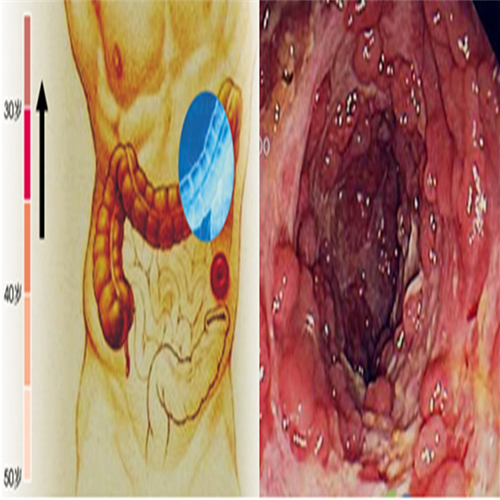

直腸息肉表現

直腸息肉的症狀